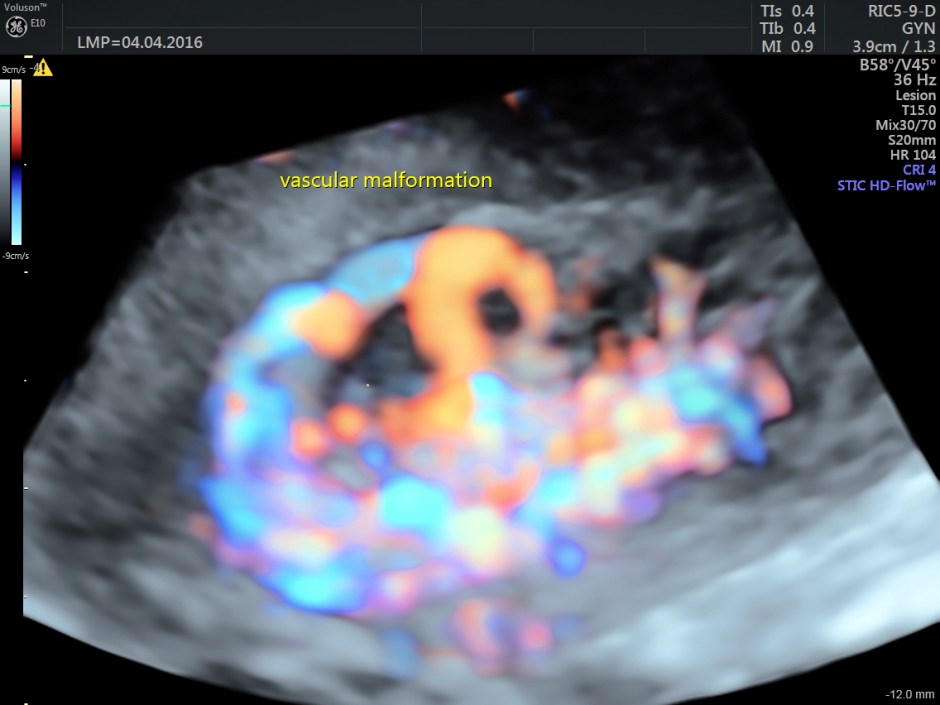

The following are the different sections of the Power Doppler reconstruction images of the trans-vaginal scan.

The following are the reconstructed 3D Power Doppler images.

The ultrasound diagnosis was a vascular malformation in the uterus .She was referred to an interventional radiologist,who did a CECT the next day.

Typically shows serpiginous/tubular anechoic structures within the myometrium with a low resistance (RI ~0.2-0.5), high velocity flow pattern on colour Doppler interrogation.